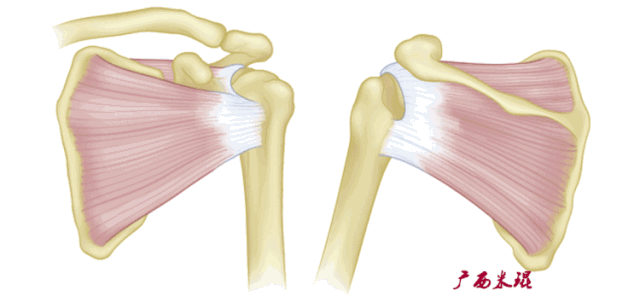

肩袖解剖

肩袖(Rotator cuff)损伤由Smith于1834年发现并命名,指组成肩袖的冈上肌、冈下肌、肩胛下肌和小圆肌的损伤。肩袖是以上4条肌腱共同组成的功能复合体,呈一个袖套状包绕肱骨头,维持盂肱关节的稳定,同时提供肩关节活动时所需的动力。

冈上肌和冈下肌在肱骨大结节上有共同止点,冈上肌和肩胛下肌在结节间沟处共同包绕肱二头肌长头腱。这样紧密的关系预示着肩袖的某一部分组织发生病变一般都会波及其余的肩袖组织,也是我们MRI阅片中必须要注意的。